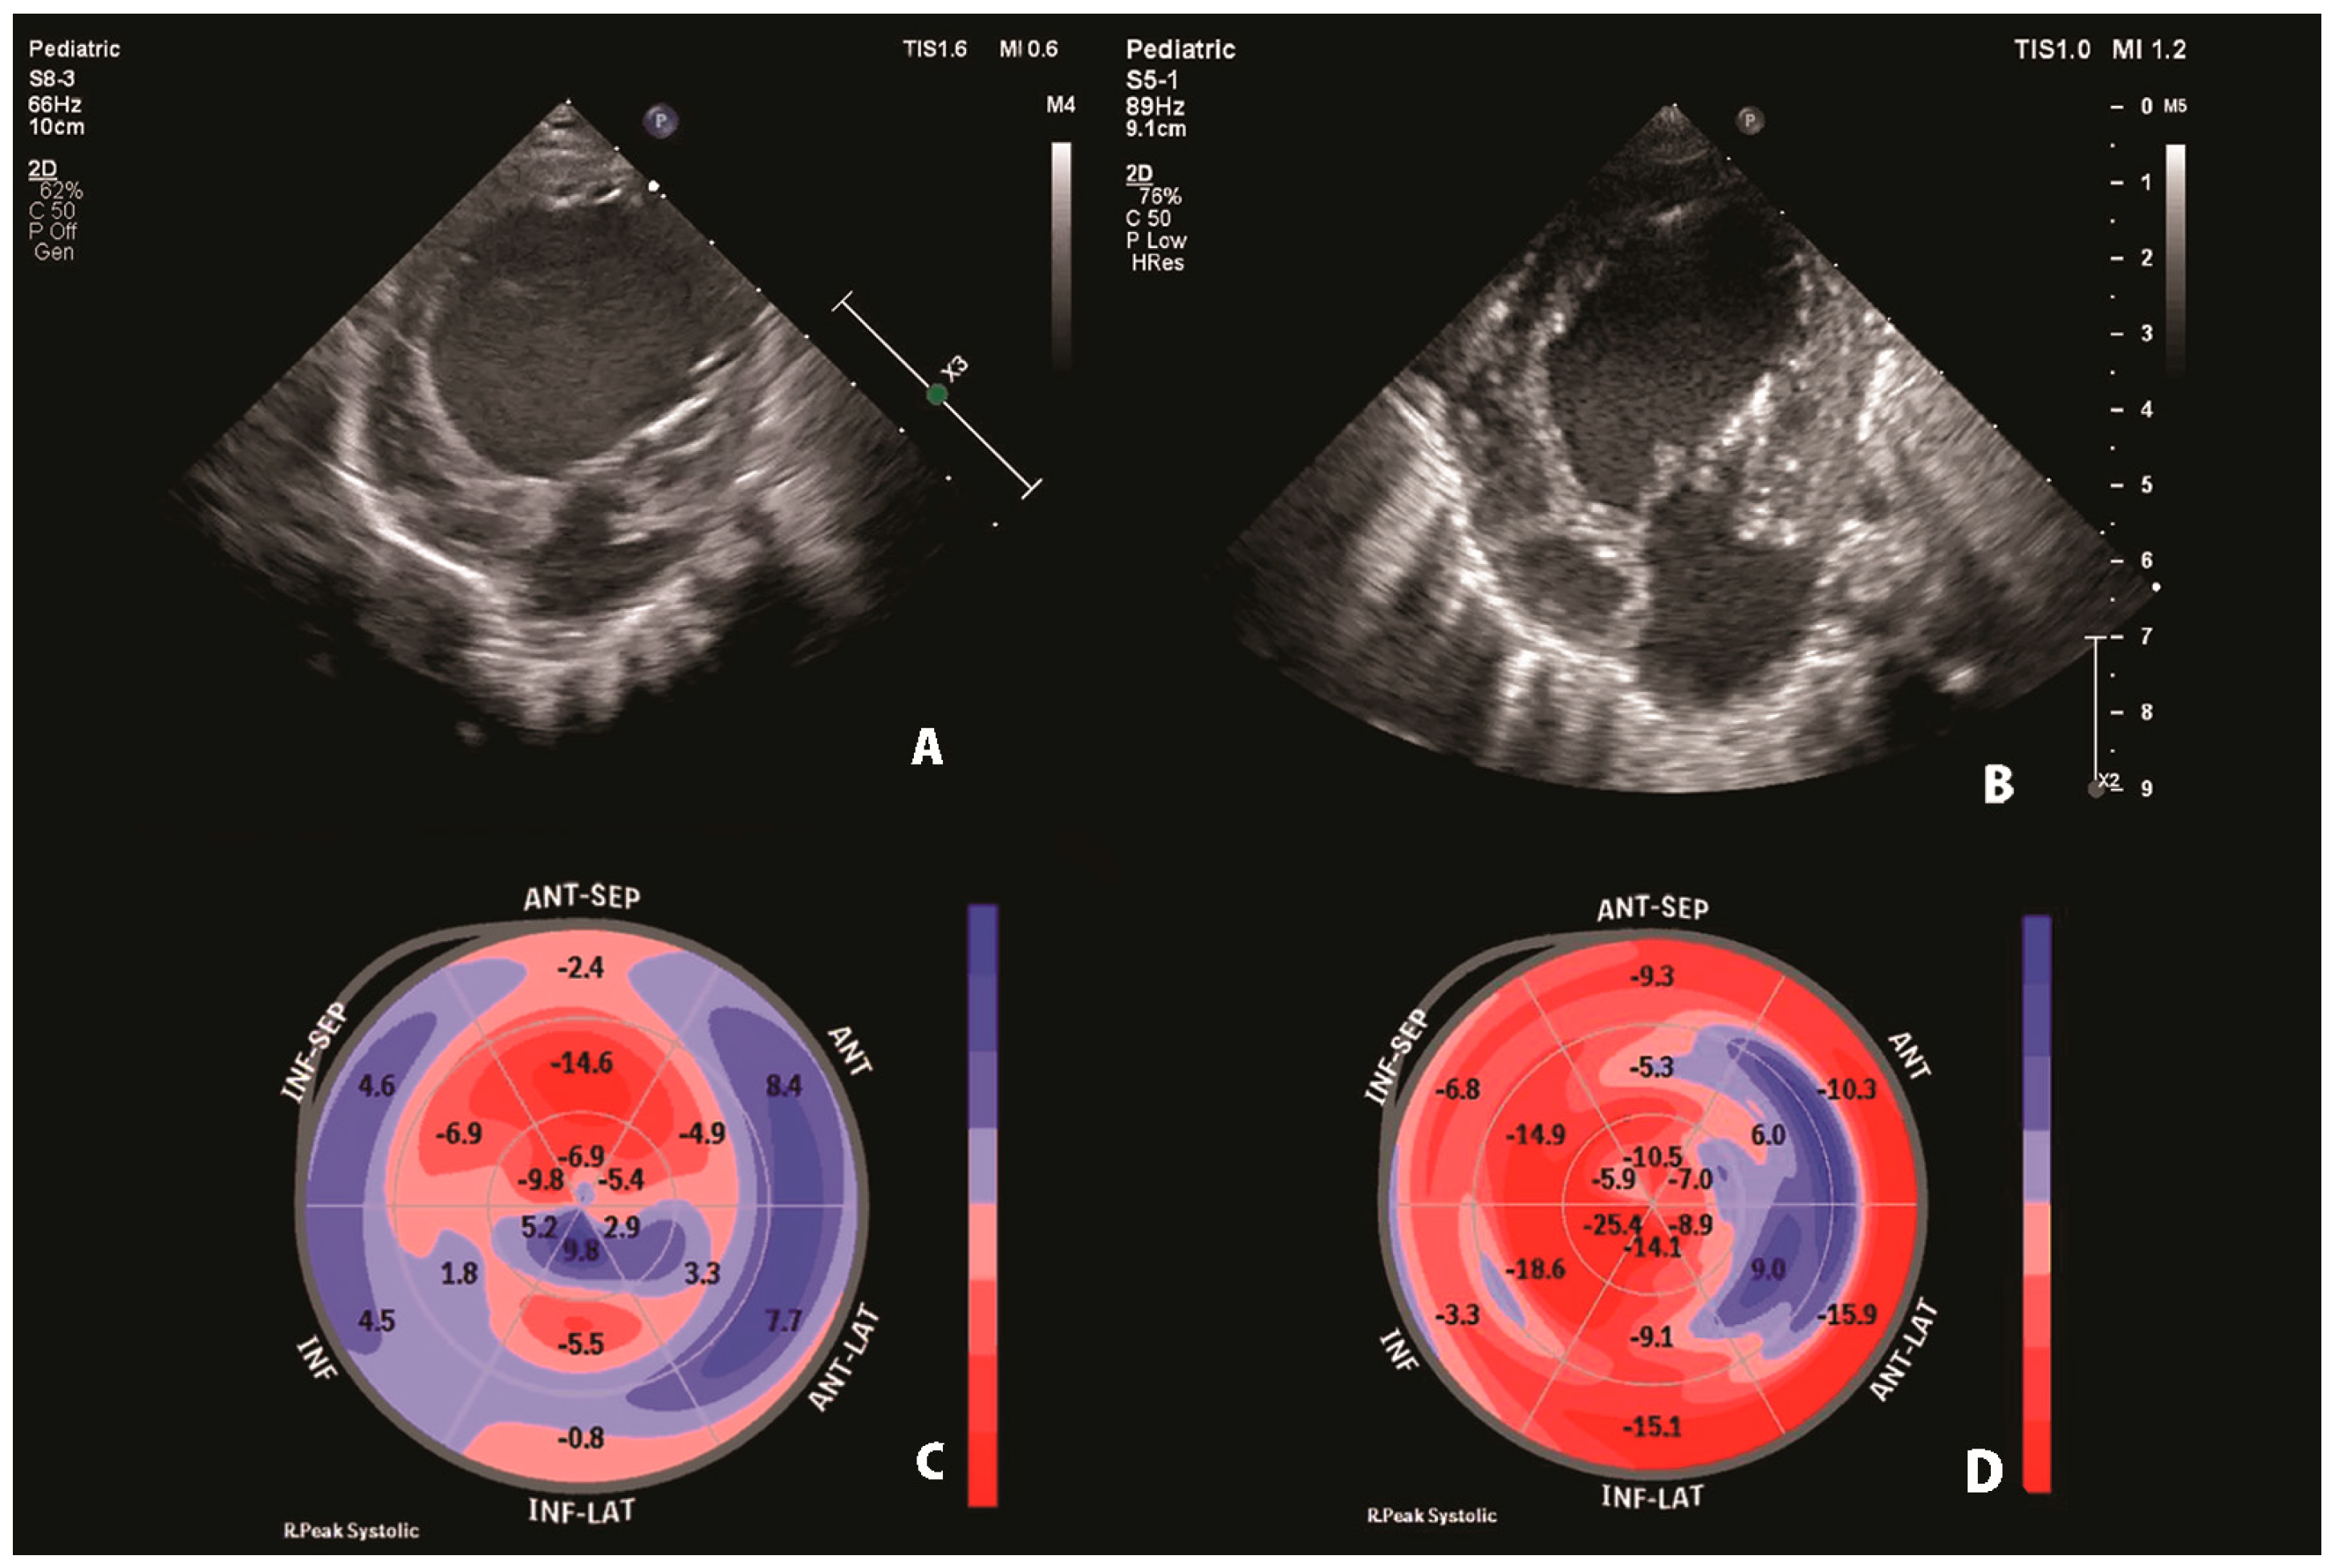

Using the Simpson method, LV EF was calculated using conventional echocardiography (18.3%). The speckle-tracking analysis assessed the regional myocardial function of individual segments and global longitudinal strain (GLS). Longitudinal strain measurements of the LV were low in all views (two-chamber: −5.6%, three-chamber: −3.6% and four-chamber: −4.6%), with impaired GLS (−4.4%). The analysis revealed hypokinetic anterior, anterolateral, and inferior LV regions with a hypokinetic septum, corresponding to territories supplied by both the LCA and the right coronary artery (RCA) (Figure 2).

Figure 2. Preoperative speckle-tracking analysis. LV longitudinal strain from the apical two, three and four-chamber view. Time-strain curves show a pathological deformation in the anterior, anterolateral, and inferior LV regions with a hypokinetic septum. Final bull’s-eye plot reveals low global longitudinal strain with severe impairment of both left and right coronary artery territories that supply the left ventricle. AP2: apical two-chamber view; AP3: apical three-chamber view; AP4: apical four-chamber view; EDV (bi-plane): end-diastolic volume (bi-plane); ESV (bi-plane): end-systolic volume (bi-plane); EF (bi-plane): ejection fraction (bi-plane); Global Endo Peak L. Strain (GLS): global longitudinal strain; and HR: heart rate.